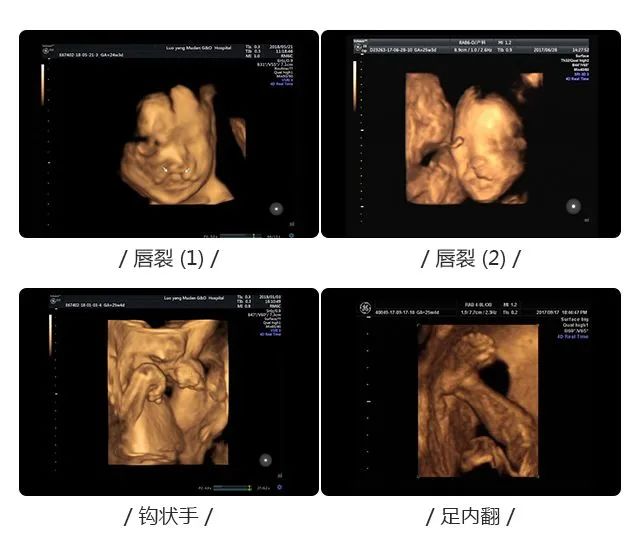

大排畸通过影像学的手段不仅可以对胎儿大小进行一个检查,还能排查胎儿重大结构畸形,比如无脑儿、脑膜脑膨出、脊柱裂、严重胸腹壁缺损、单腔心、致死性软骨发育不良等等。